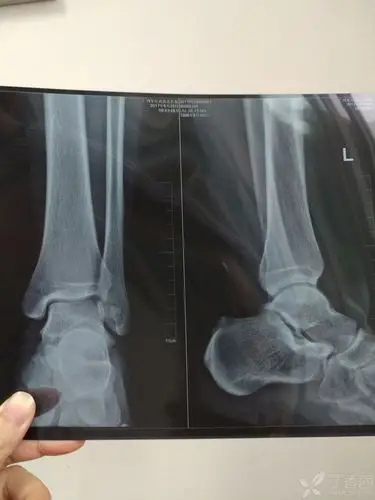

距骨骨折关节镜治疗

请骨科战友帮忙看一下左踝关节x线片 [病例帖]

行跟骨牵引10天后行内固定术,下面是术前和术后的片子,该患者左踝部